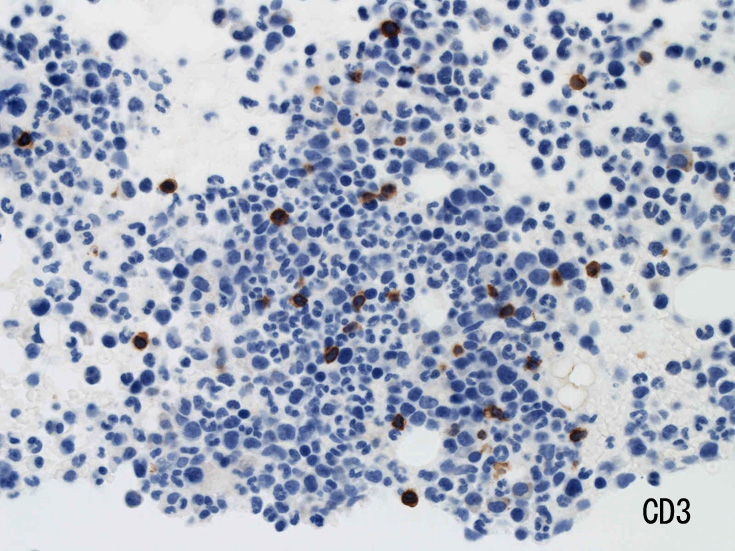

骨髄免疫染色およびISH

MG染色での大型異型細胞はCD56, CD30陽性。CD3は陰性を示す